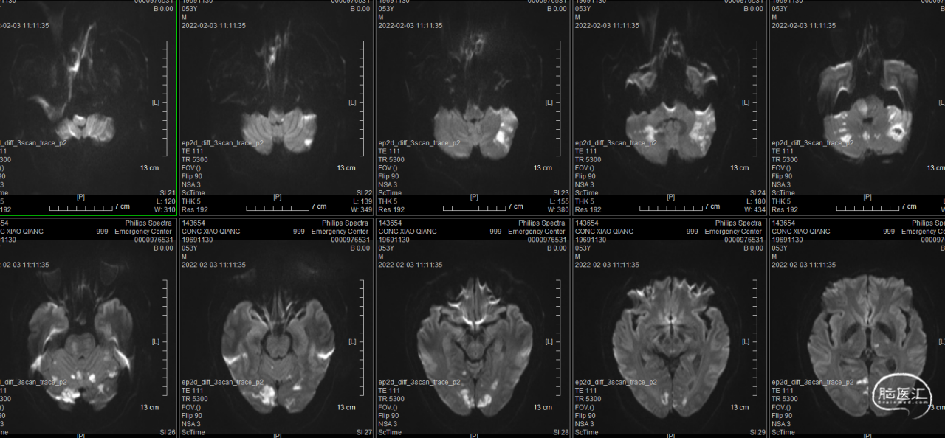

术后核磁(2022-2-3)